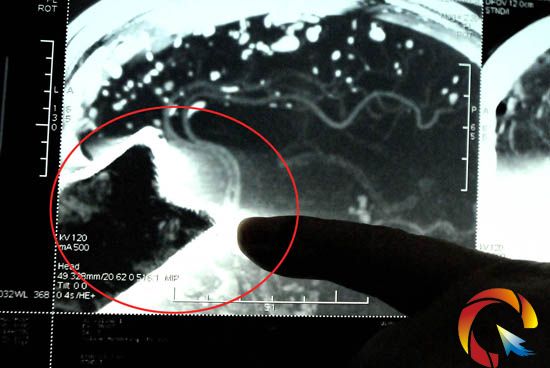

“插进颅脑中的刀片有7厘米长。”据黔东南州医院神经外科专家杨勇灵介绍,当日上午10时许,家住雷山县西江镇小龙六组的40岁农妇周蔸往,在家中利用简易的猪菜粉碎机切割与粉碎猪菜时,粉碎机高速运转中的一块刀片,突然飞出从周的面部斜插进颅脑中。该刀片长约20厘米、宽约5厘米,而插入颅脑中的刀片有约7厘米长。

刀片插入颅脑长7厘米、宽5厘米

“像这样的病患较罕见,手术不成功的话患者可能就会在手术台上即刻死去。”杨勇灵告诉记者,“在患者入院后,我们先对其进行了全面捡查,发现插入周颅脑中的刀片末端距大脑前动脉血管仅有5毫米,一旦在手术中稍有不慎或有轻微的摇动刀片,大脑前动脉血管破裂,出现大出血,周即会当场死在手术台上。

刀片末端离大脑前动脉仅5毫米